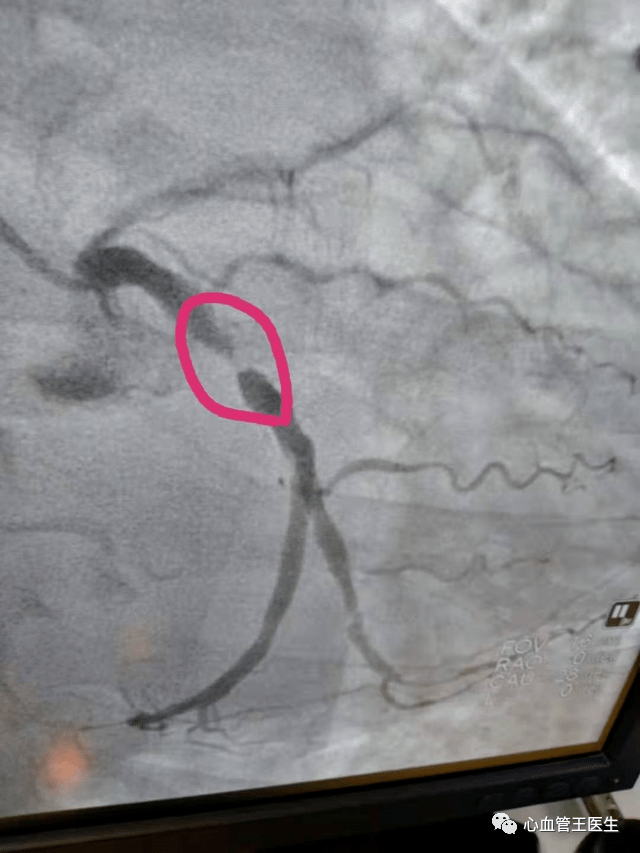

冠状动脉造影示前降支中段局限性狭窄约90%